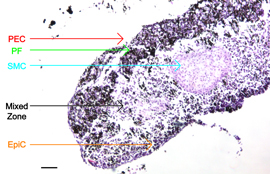

| This microscopic image shows the structure and layers of in vitro bronchiole tissue created at Rice University and Nano3D Biosciences. The cell layers include epithelial cells (EpiC), smooth muscle cells (SMC), pulmonary fibroblasts (PF) and pulmonary endothelial cells (PEC). CREDIT: Hubert Tseng/Rice University |

Houston, TX | Posted on January 24th, 2013The research is part of an international trend in biomedical engineering to create laboratory techniques for growing tissues that are virtually identical to those found in people's bodies. In the new study, researchers combined four types of cells to replicate tissue from the wall of the bronchiole deep inside the lung.

Nano3D Biosciences won a Small Business Innovation Research (SBIR) grant from the National Science Foundation (NSF) in 2011 to create a four-layered lung tissue from endothelial cells, smooth muscle cells, fibroblasts and epithelial cells.

Tseng said the new tissue resembles native bronchiole tissue more closely than any other tissue yet created in the lab.

"We conducted a number of tests, and the tissue has the same biochemical signature as native tissue," Tseng said. "We also used primary cells rather than engineered cells, which is important for toxicological testing because primary cells provide the closest possible match to native cells."